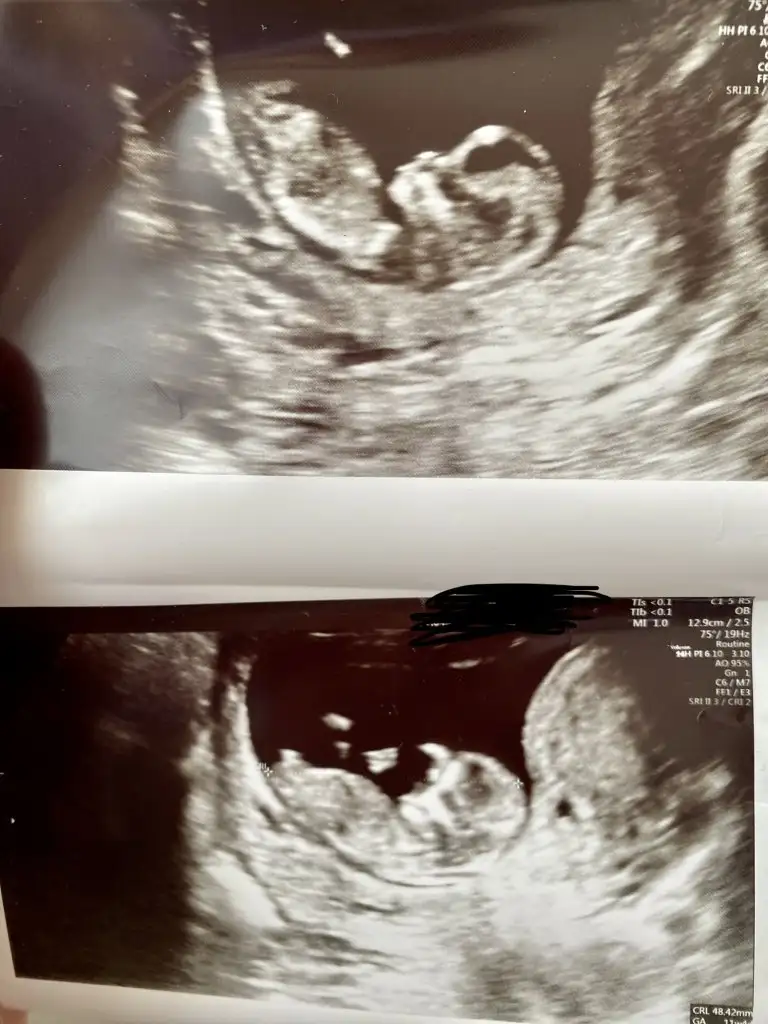

Maşallah , ama çok erken şuanKızlar 11 haftalık. Var mı cinsiyet tahmini yapabilen ?

Bana kız gibi geldiKızlar 11 haftalık. Var mı cinsiyet tahmini yapabilen ?